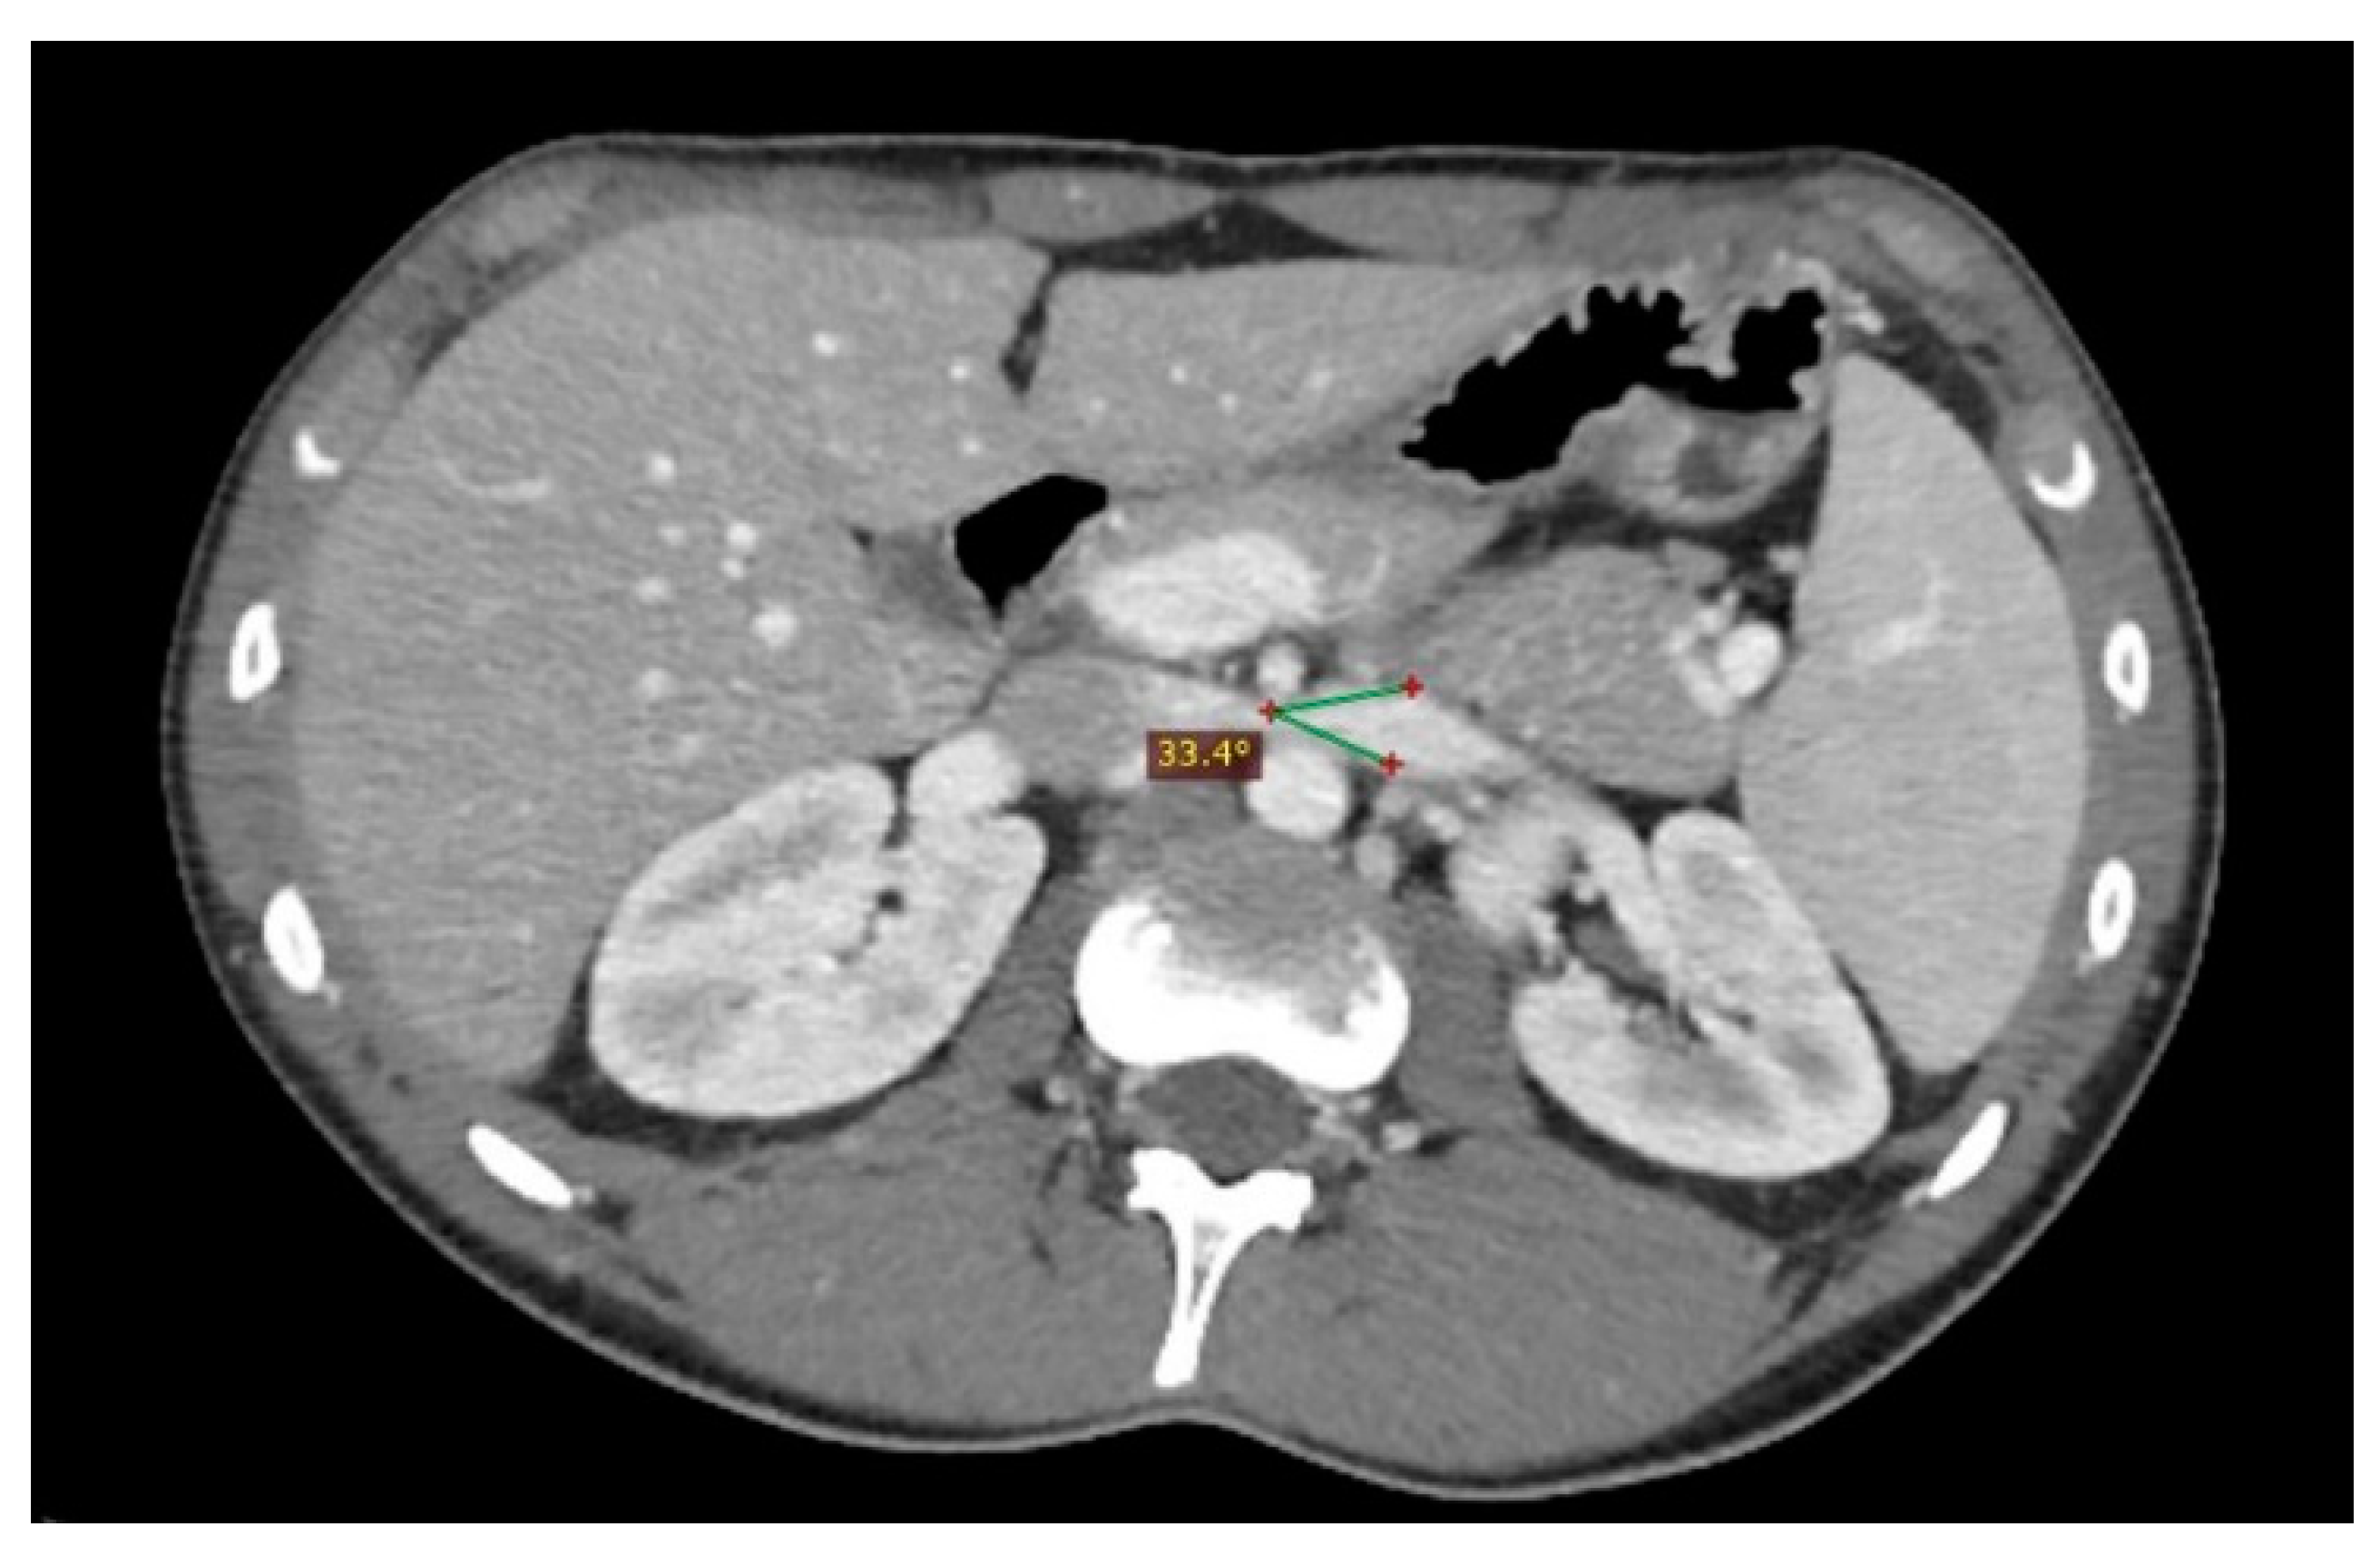

Nutcracker syndrome (Radiopaedia 6459373473 B) NC Commons Nutcracker Syndrome Genetic    the nutcracker syndrome is a rare clinical entity caused by compression of the left renal vein (lrv) by the superior.   the nutcracker syndrome (ncs) is defined by compression of the left renal vein (lvr) and may present with a wide.  a rare, syndromic renal disease characterized by the entrapment of left renal vein (lrv) between the superior.. Nutcracker Syndrome Genetic.

Nutcracker Syndrome (Radiopaedia 5702463896 B) NC Commons Nutcracker Syndrome Genetic    nutcracker syndrome, or left renal vein entrapment, describes an uncommon condition involving compression of the left renal vein, usually.  renal nutcracker syndrome (ncs) is a condition that occurs when the left renal vein (the vein that carries blood purified by the.  a rare, syndromic renal disease characterized by the entrapment of left renal vein (lrv) between the. Nutcracker Syndrome Genetic.